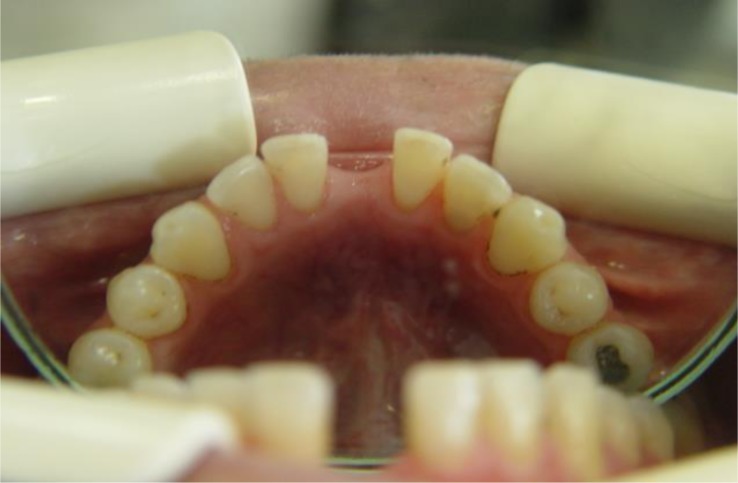

Fig 2.

An occlusal view of the missing mandibular incisor